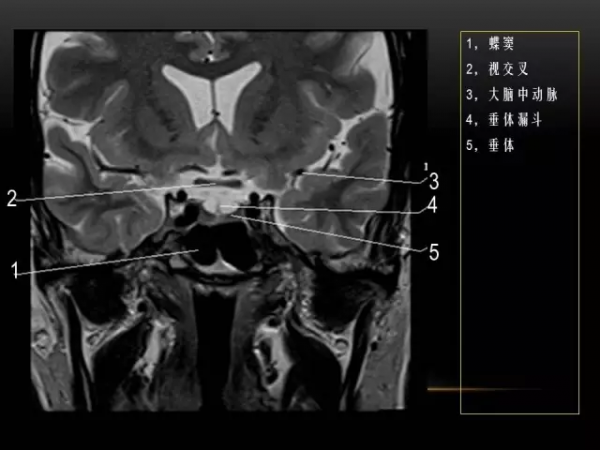

MRI下眼部及鼻竇的冠狀位解剖